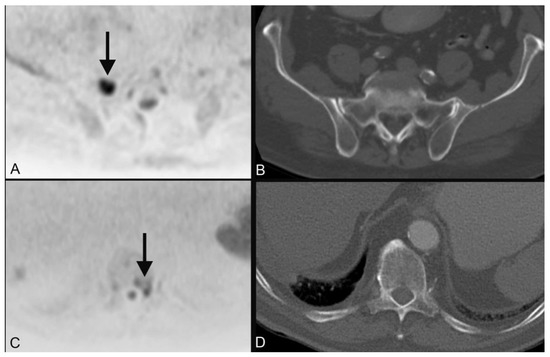

| 1 | plasmocytoma (Figure 3) | ||

| 28 | hypopharyngeal carcinoma (Figure 2) | pT2 pN2b cM0 | squamous cell carcinoma |

| 28 | hypopharyngeal carcinoma (Figure 2) | primary chemoradiotherapy |